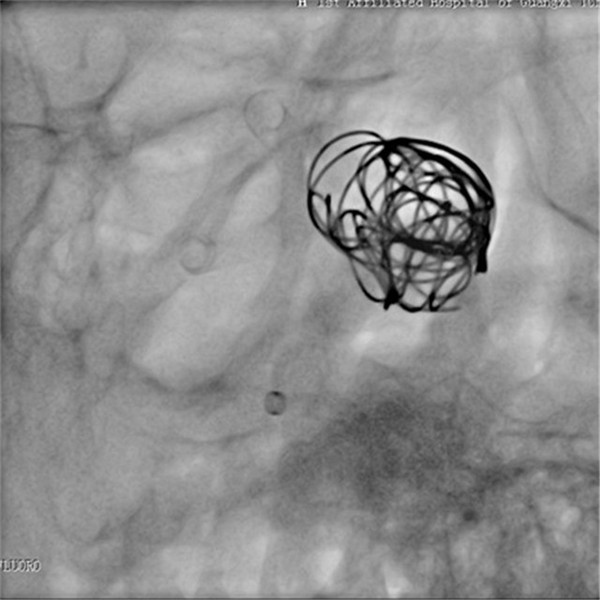

手术在气管插管全麻下进行,微导管顺利送到理想位置,由于出现血管痉挛,立即行解痉处理,好转后置入血流导向装置,由于瘤腔血流速度快,置入弹簧圈支撑支架,并缓慢释放装置,经造影显示动脉瘤消失,载瘤动脉通畅。手术过程顺利,术后患者神志清醒,言语切题,视力无异常改变,四肢活动正常,患者已缓慢下床活动,手术获得圆满成功。手术当日有来自广西区内多家医院神经外科主任的现场观摩与交流。

密网支架置入